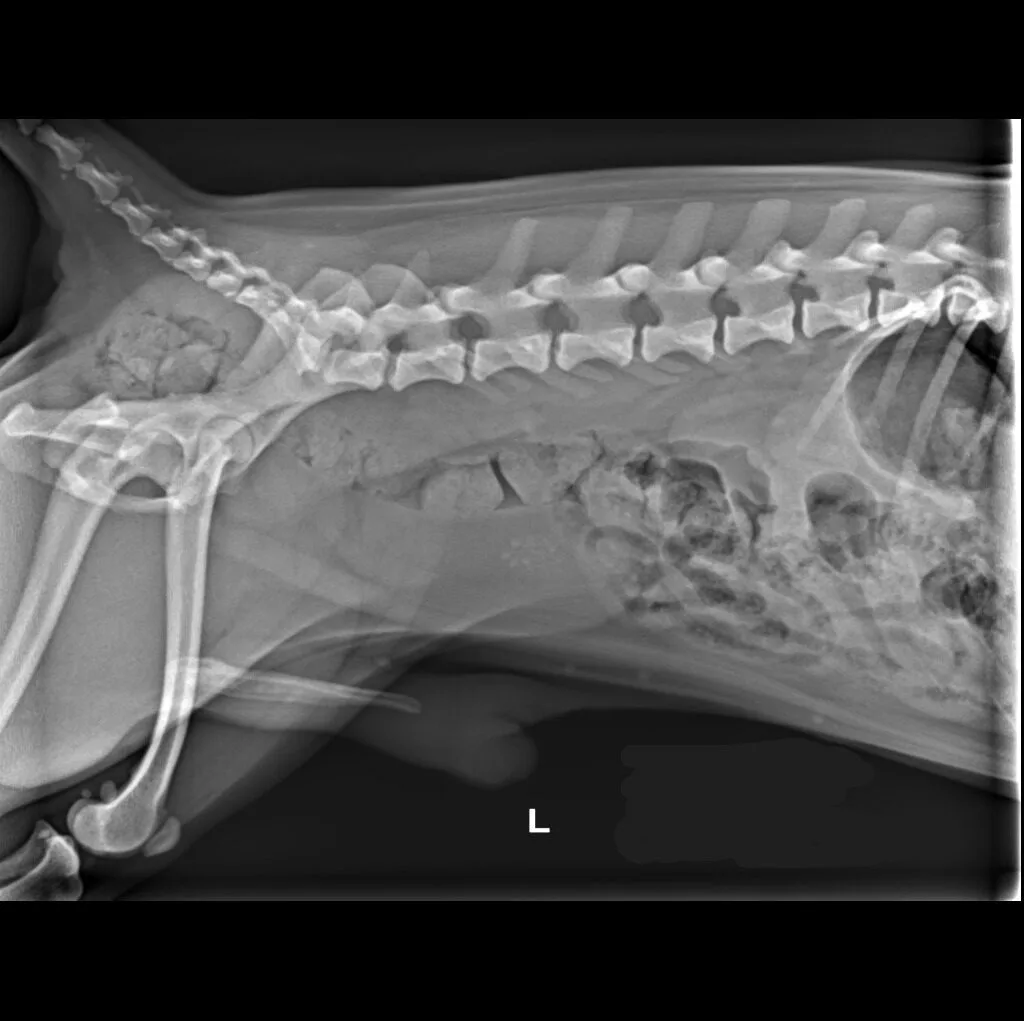

At Grand Ave. Pet Hospital, we utilize digital radiography to diagnose and monitor a wide range of medical conditions in pets. Digital X-rays provide clearer images, faster results, and safer radiation levels, ensuring the best possible care for your furry companion.

Digital radiography offers superior imaging quality and precision compared to traditional X-ray techniques. It allows us to detect hidden health issues early, leading to faster and more effective treatments.

🔹 Abdominal & Gastrointestinal Issues – Detecting obstructions, tumors, or organ abnormalities

🔹 Cancer Screening – Locating tumors and assessing disease progression